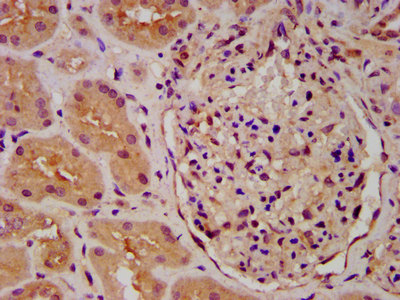

IHC image of CSB-PA622660LA01HU diluted at 1:600 and staining in paraffin-embedded human kidney tissue performed on a Leica BondTM system. After dewaxing and hydration, antigen retrieval was mediated by high pressure in a citrate buffer (pH 6.0). Section was blocked with 10% normal goat serum 30min at RT. Then primary antibody (1% BSA) was incubated at 4°C overnight. The primary is detected by a biotinylated secondary antibody and visualized using an HRP conjugated SP system.